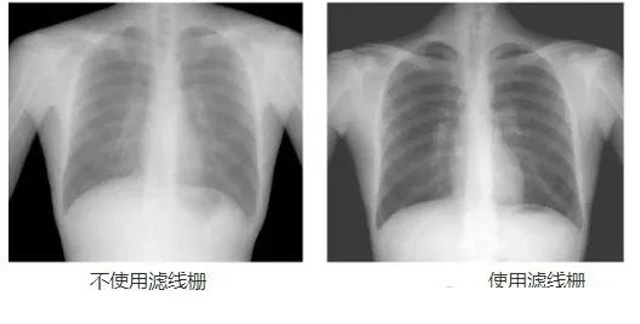

DR影像X射線在醫(yī)學(xué)檢查成像有著廣泛的使用。但是它的散射線影響成像質(zhì)量問(wèn)題。濾線柵的發(fā)明使用很好的解決了這個(gè)問(wèn)題,構(gòu)造簡(jiǎn)單鉛條粗,密度和柵比規(guī)格單一,能減散射線但吸收較多原發(fā)射線。伴隨這醫(yī)療影像設(shè)備技術(shù)的發(fā)展,這個(gè)濾線柵的工藝制造技術(shù)有改進(jìn),鉛條變薄,柵密度和柵比有更多的選擇。特別是材料方面有新組合,填充物也依不同成像要求優(yōu)化。特別是移動(dòng)DR這類型的DR設(shè)備的出現(xiàn),濾線柵也設(shè)計(jì)成立方便拆卸形的,方便使用。被照體情況決定是否使用,更好平衡成像質(zhì)量與射線劑量。

放置方面:置于人體與片盒間,聚焦面朝向X線入射方向,X線焦點(diǎn)放鉛條會(huì)聚線上,不能反置,X線中心對(duì)準(zhǔn)濾線柵中心,左右偏移不超3cm,傾斜X線管要與鉛條排列方向平行。攝影時(shí)焦距改變不超焦距的25%;活動(dòng)式濾線器運(yùn)動(dòng)時(shí)間至少長(zhǎng)于曝光時(shí)間的1/5;因吸收原發(fā)射線要適當(dāng)增加曝光條件;四肢薄位置一般不用濾線柵;不同千伏對(duì)應(yīng)不同柵比;立位胸片架、乳腺DR攝影等有各自特定濾線柵要求。